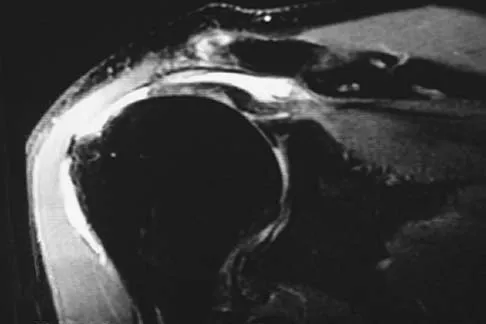

Question 75

Figures 49a and 49b show MRI scans of the shoulder. What is the most likely diagnosis?

Explanation